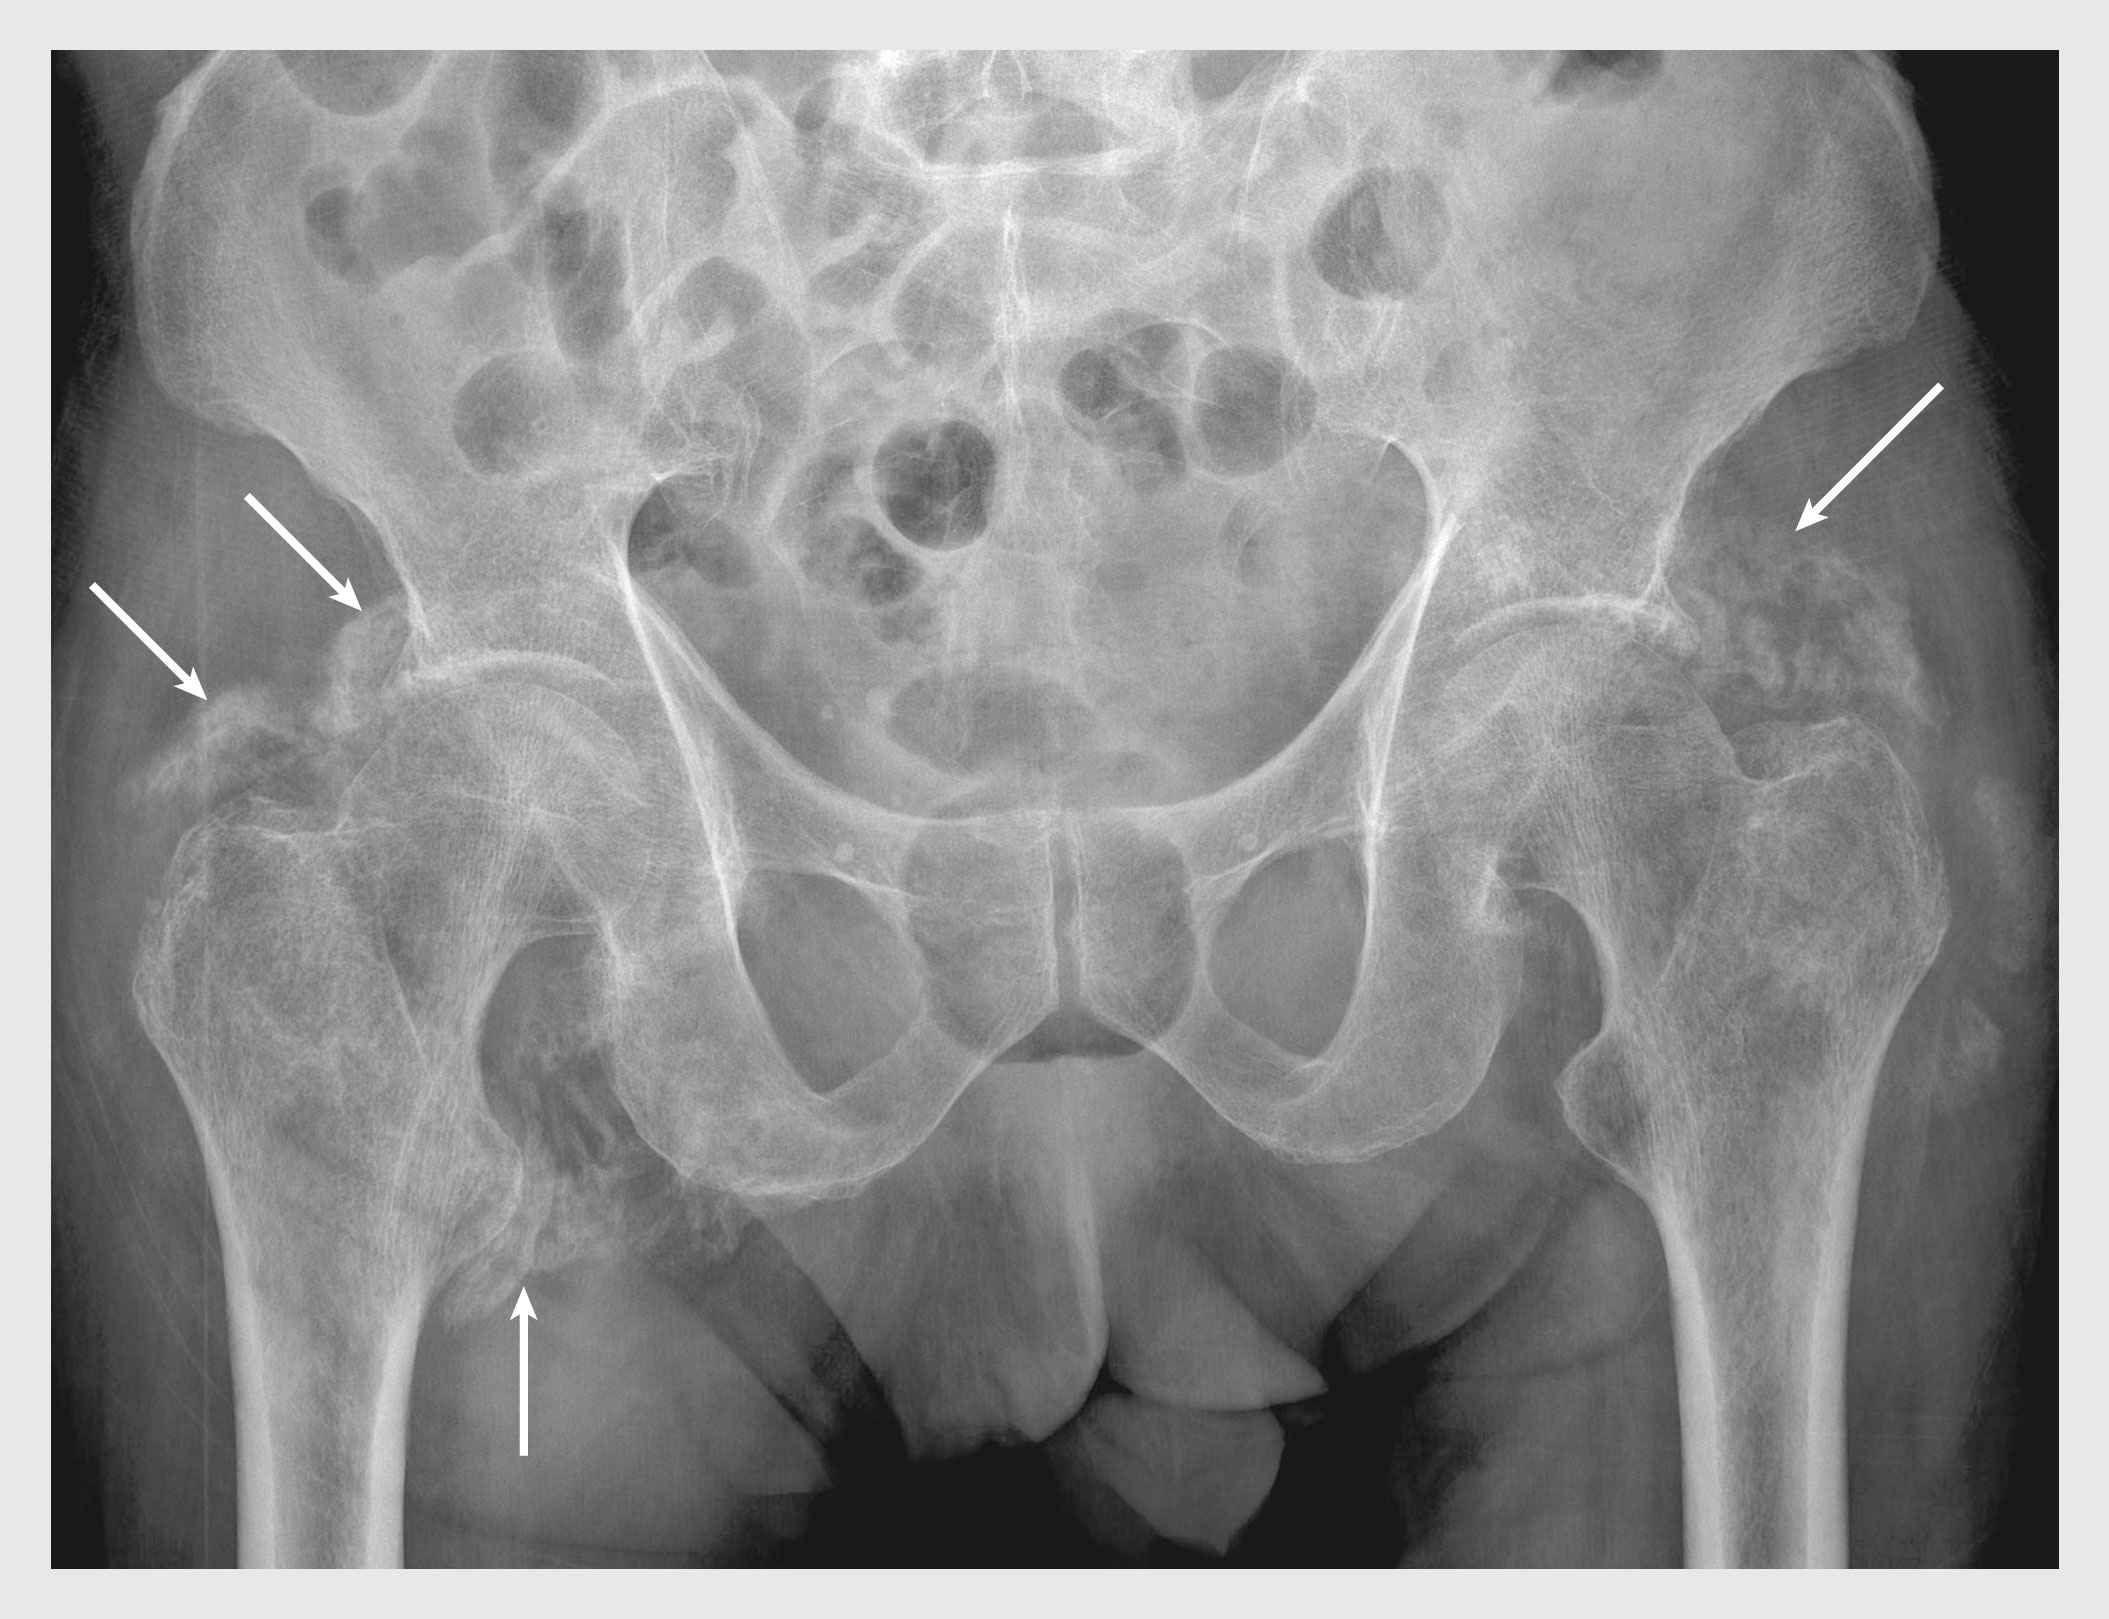

Figuur 3

Heterotope ossificaties rondom de coxofemorale gewrichten van patiënt B.

Figuur 3 | Heterotope ossificaties rondom de coxofemorale gewrichten van patiënt B.

Röntgenfoto van het bekken van patiënt B. De heterotope ossificaties rondom de coxofemorale gewrichten zijn met pijlen aangegeven.